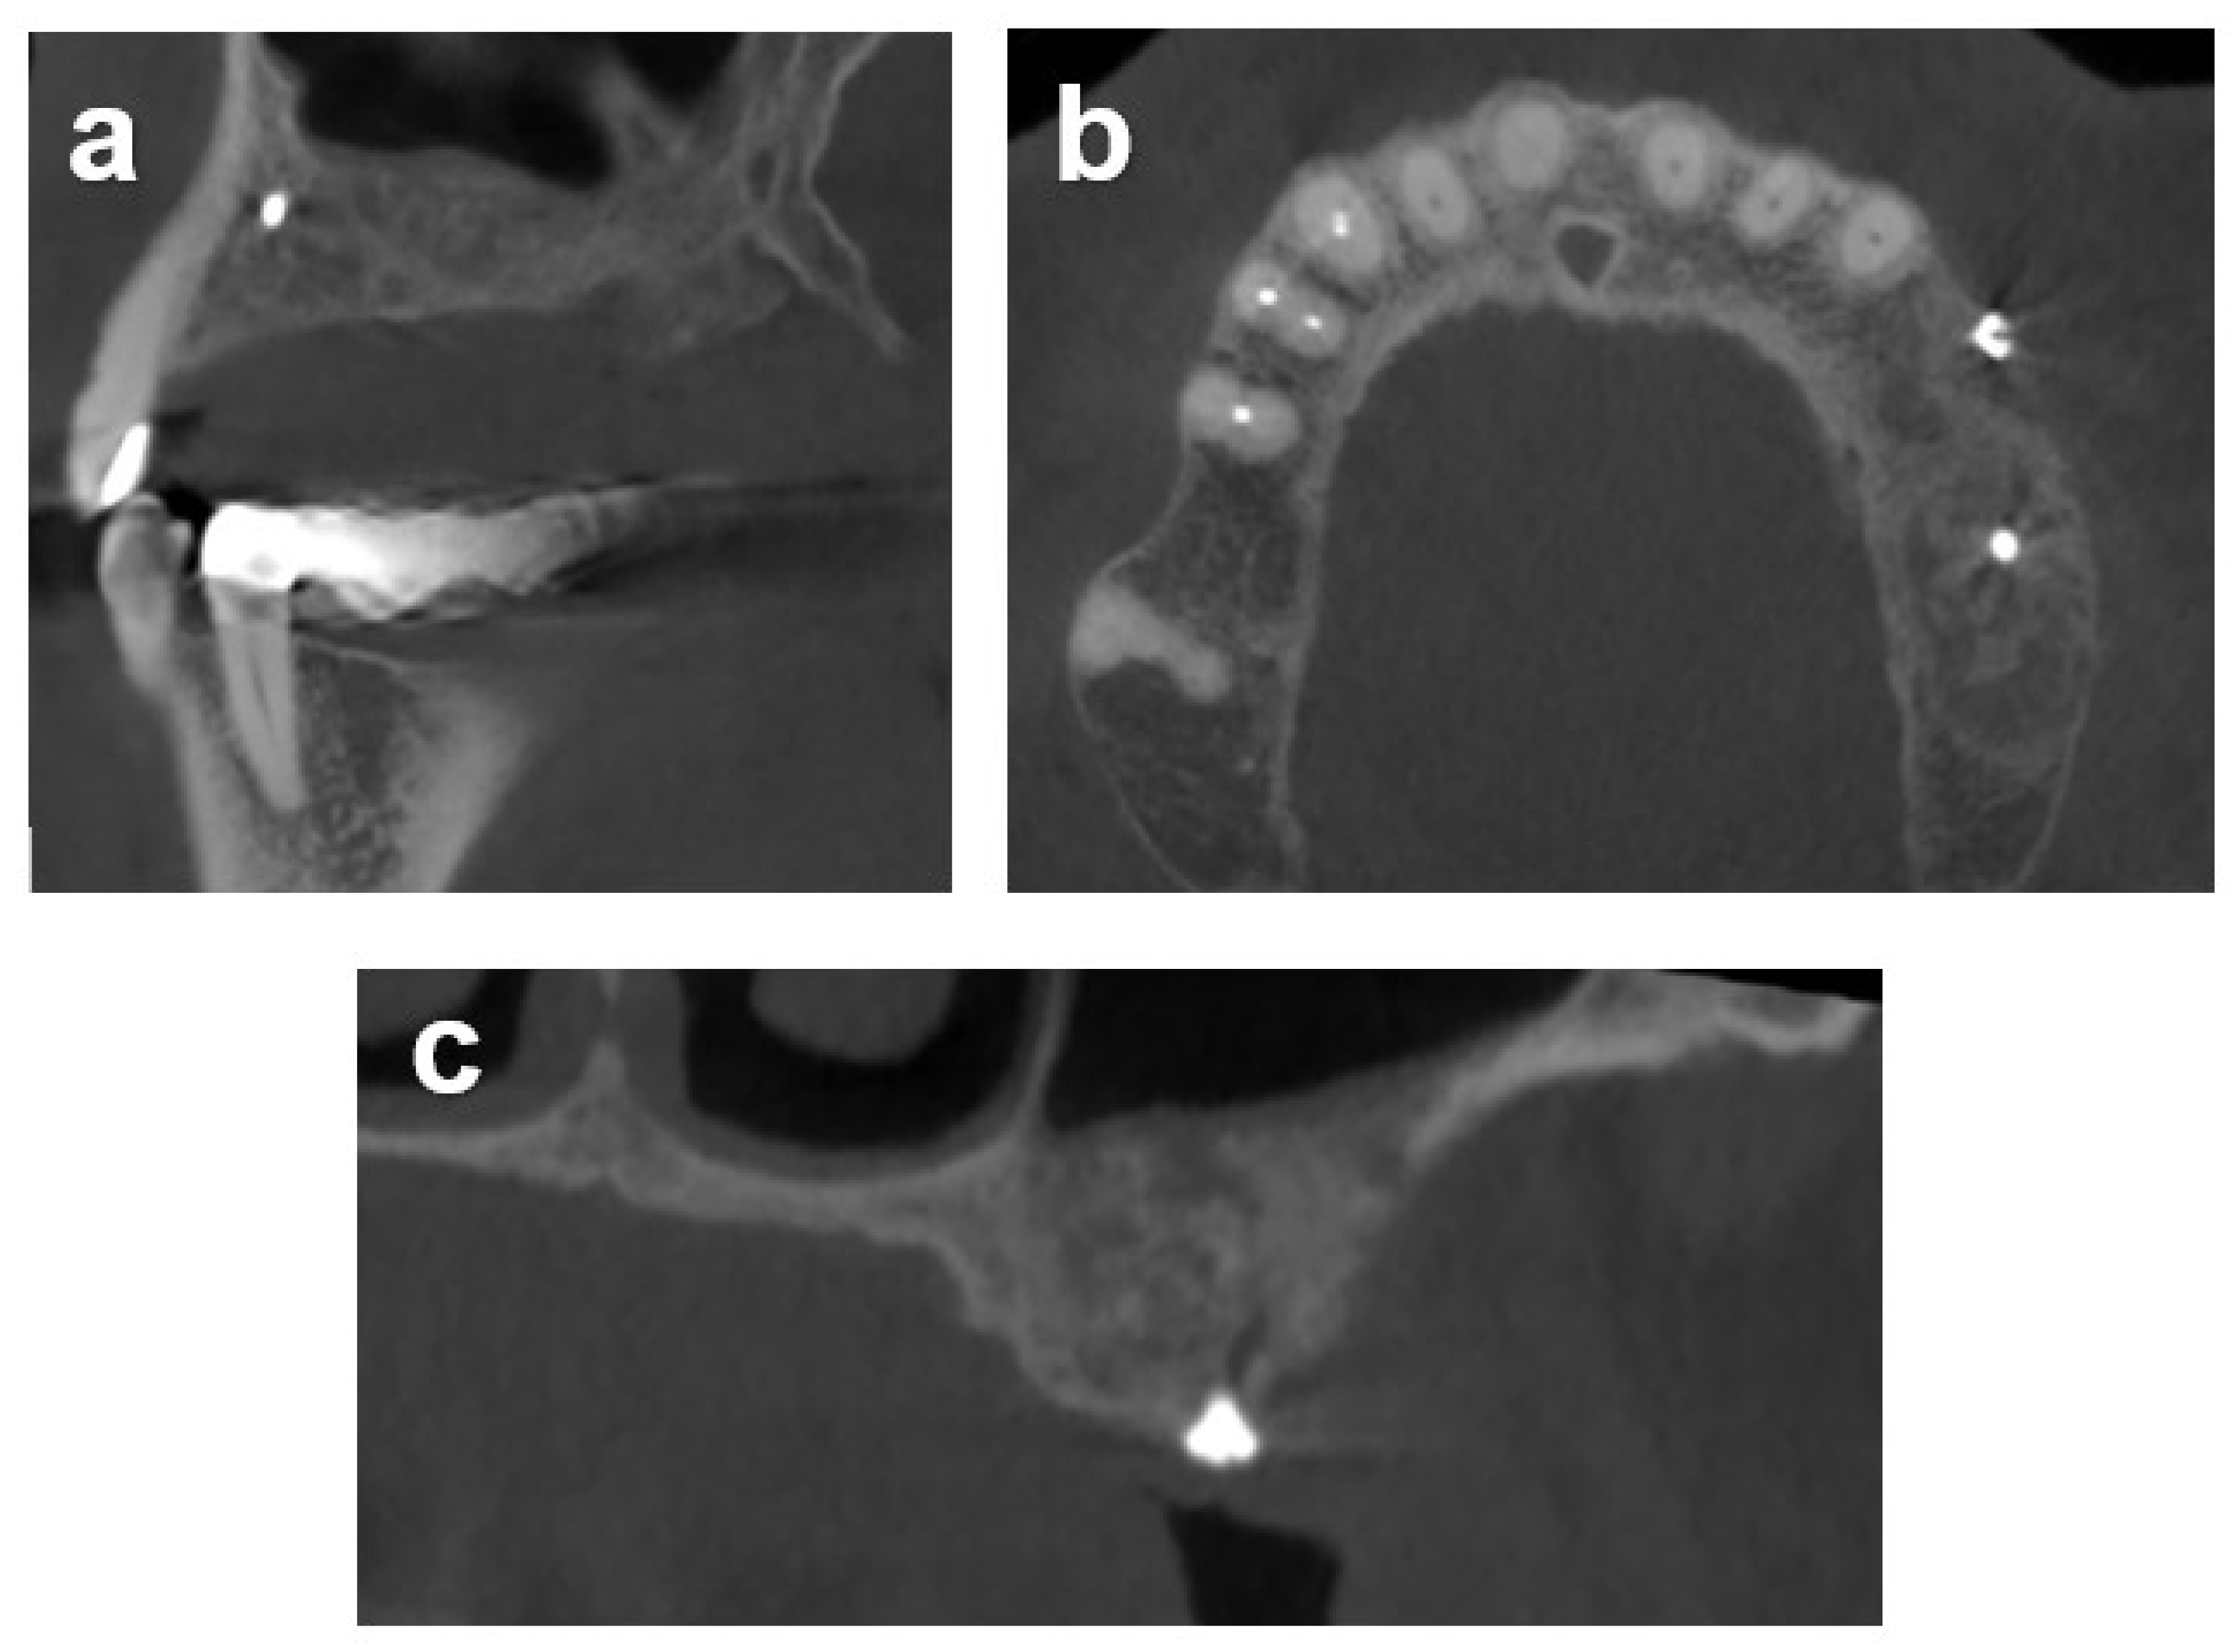

2.7.1. Case 1

2.7.2. Case 2

2.7.3. Case 3

3.2. Radiometric Assessment